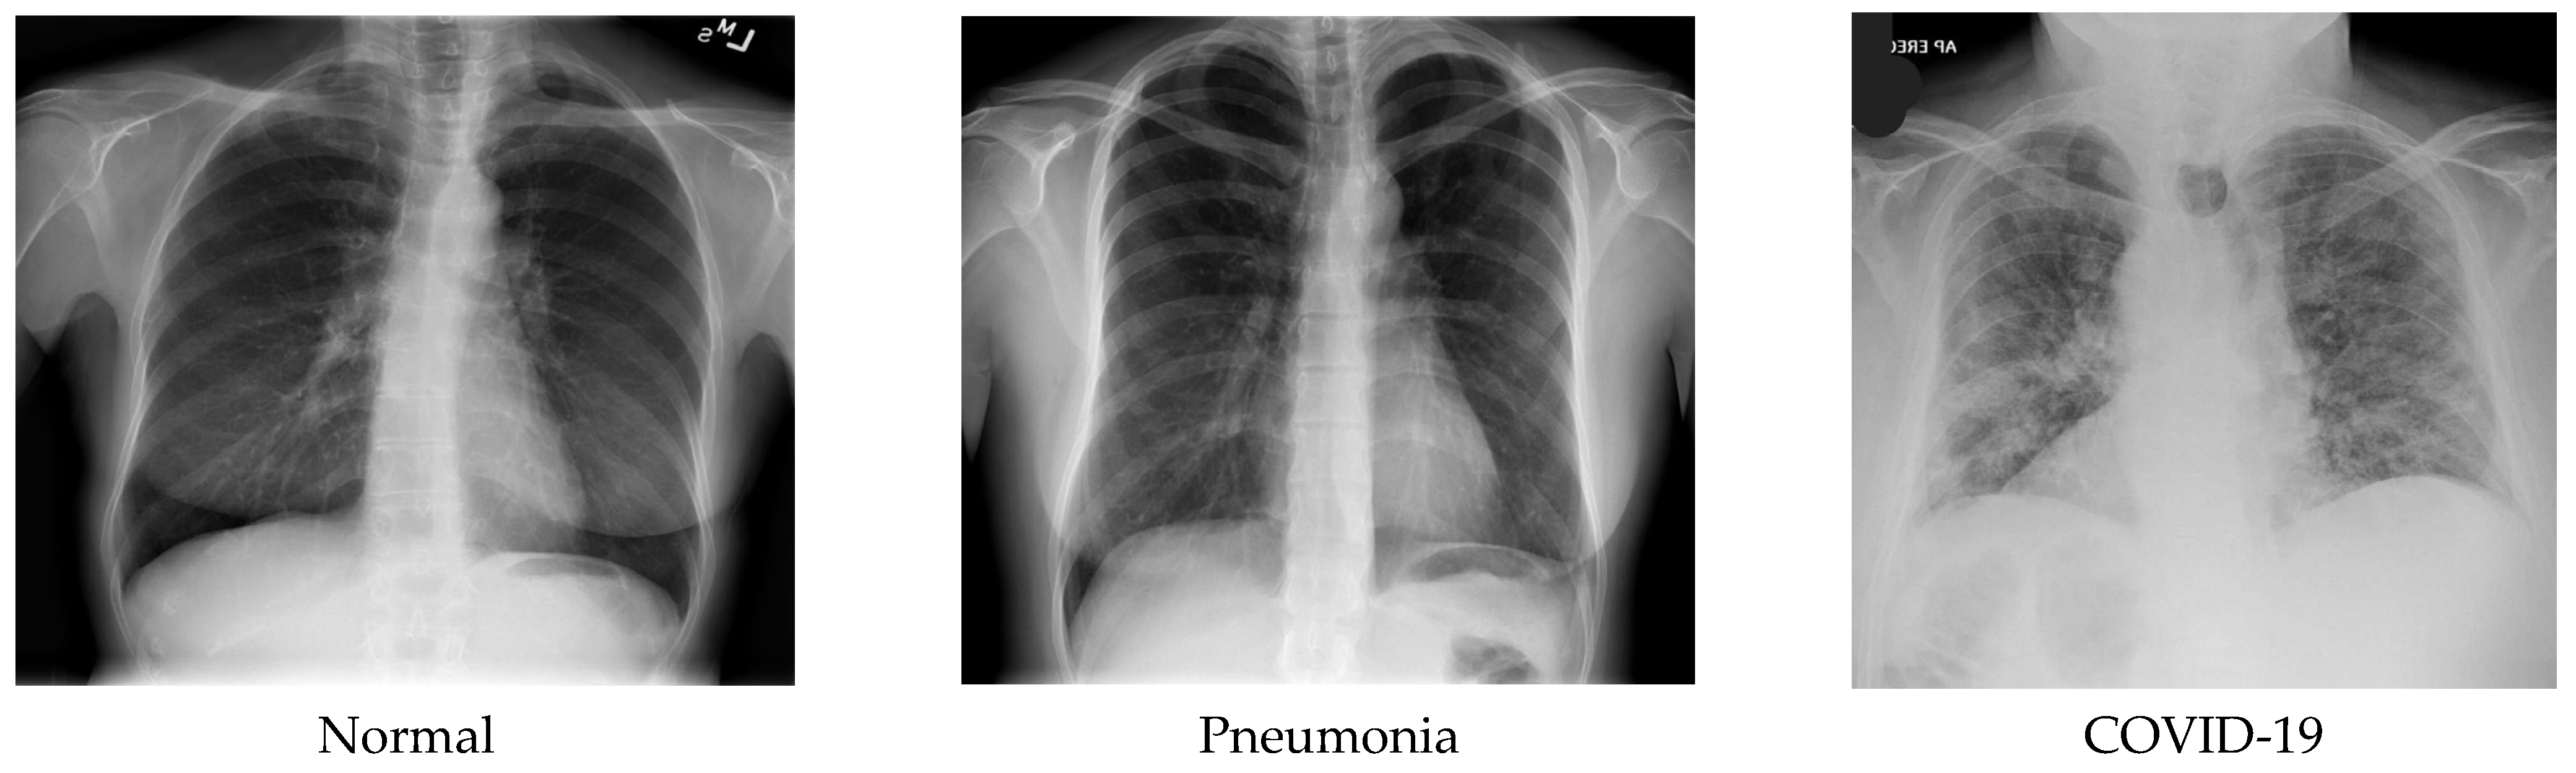

A data set of X-ray scanned images has been assembled in the three-level classification. One with the label “Non-COVID-19 X-ray”, another class labeled “COVID-19 X-ray”, and the last one labeled “pneumonia Chest X-ray” were used for trial-and-error purposes. The dataset consists of 3312 images, of which pneumonia-affected and normal patient X-rays were 694 images each, and COVID-19-affected patients’ X-rays were 1924 images from publicly available primary datasets [22,23]. Among these, 2020 random images have been selected. Afterward, the whole dataset was split into 85% for training and 15% for testing. Note that some of the most prominent biases in X-ray imaging datasets are demographic bias, illness prevalence bias, data collection bias, labeling bias, and technical bias concerning equipment conditions. Biases in X-ray image datasets can have a major impact on the performance of DL models, resulting in erroneous diagnoses, inequities in treatment, and decreased faith in the technology. To maintain the fairness of the proposed model, these biases were reduced by forming a novel dataset from the combination of two separate X-ray imaging datasets. Furthermore, the dataset was divided into three classes without a significantly high sample imbalance between classes. When looking at the chest X-ray data set, it can be noticed that these three categories seem to be closely related. Figure 1 shows some sample images of the dataset.

Figure 1. Sample images of the dataset.